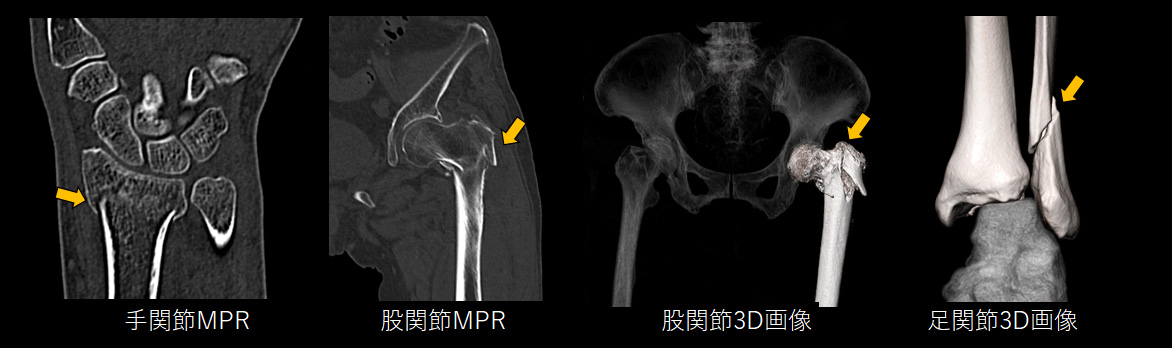

整形領域 では細かな骨折を発見する高精細な画像を作成

整形領域では、骨折の有無やその重症度を把握するためにより詳細なCT検査が役立ちます。

整形領域では他の部位の検査と比較して低被ばくかつ短時間で検査が可能であることから、小児から高齢者まで安心して検査を受けていただけます。CT撮影後は、診療放射線技師が「MPR画像」や「3D画像」と呼ばれる高度な画像を作成することで、骨折の程度を正しく判断し、患者説明や手術の際に役立てています。

3D画像 を用いた手術シミュレーションにより安全な手術を提供

CT検査で撮影した画像を最大限有効活用して、診断用・治療用・患者様説明用に3D画像を作成しています。3D画像は、CT画像と比べて多彩かつ立体感があるため、誰が見ても病態を理解しやすい特徴があります。また医療従事者にとっても手術のシミュレーションをする際に欠くことのできない存在です。

これらの精細な画像を機械的に作成することは困難であり、非常に多くの知識と高度な技術が必要となります。当院では人の手による高精細かつ丁寧な画像提供を行っています。